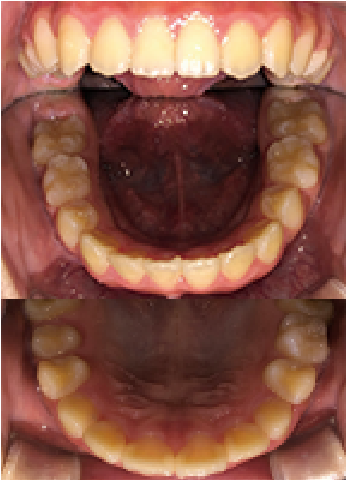

症例 : 9歳 男性

Before

After

主訴

反対咬合(受け口)

治療方法

プレオルソ+インビザファースト

総額治療費

660,000円(税込)

治療期間

6ヶ月

治療のリスク・副作用

下顎の後退中に顎に痛みを感じることがあります。

改善ポイント

上顎の拡大のためインビザラインファーストを行いつつ、上下関係を改善させるためにプレオルソを就寝時に着用し、下顎の後退を期待しました。